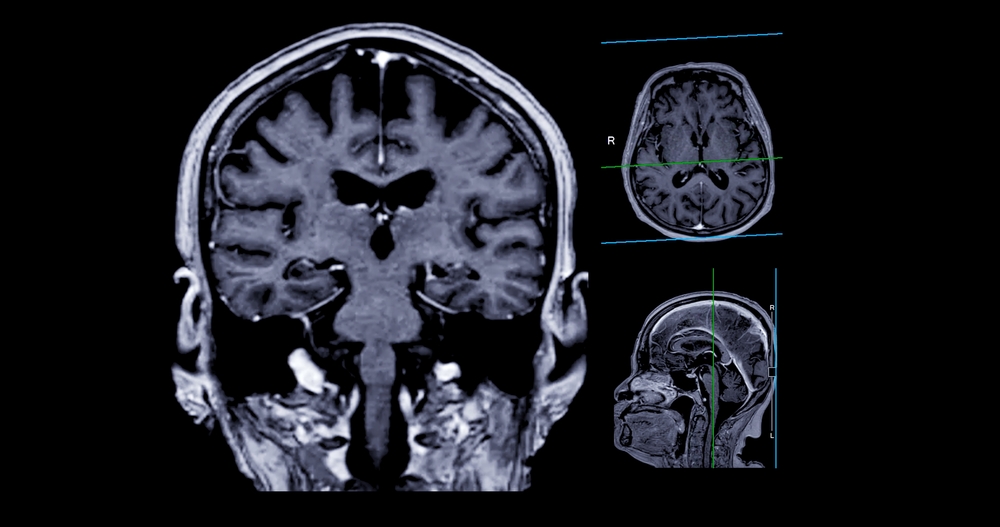

Alzheimer’s disease is a tauopathy. Along with other brain changes, abnormal tau disrupts the neuronal “highway system,” contributing to cognitive decline.